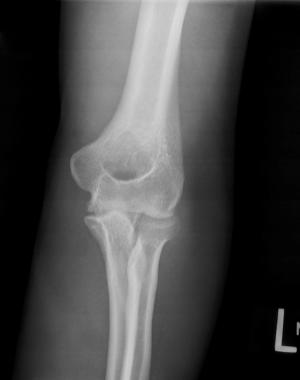

Image IQ: 23-year-old Male with Elbow Pain

ByMatthew Minn, MD,James Jelinek, MD

August 7th 2014

23-year-old male with a known undisclosed disease presents with left elbow pain.

• Image IQ: 23-year-old Male with Elbow Pain

Published: August 7th 2014 | Updated: